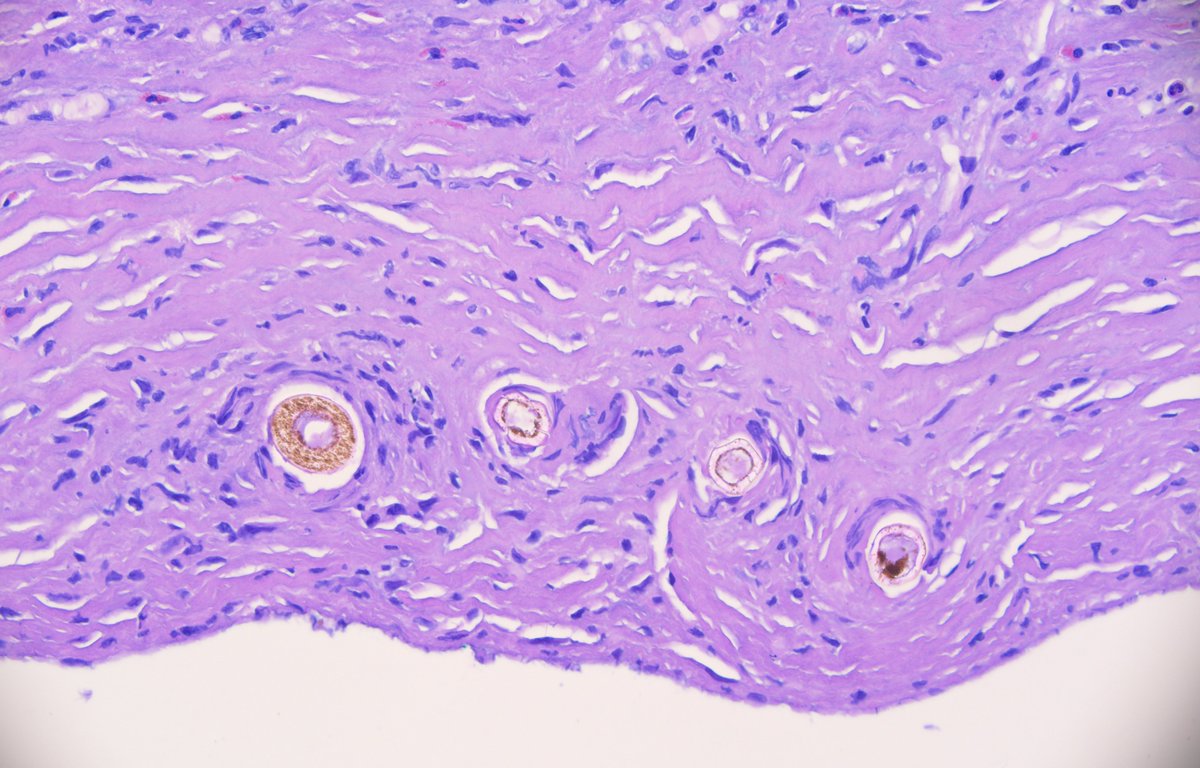

What are these structures doing in a piece of peritoneal tissue from a continuous ambulatory peritoneal dialysis catheter site? #PathTwitter #pathology